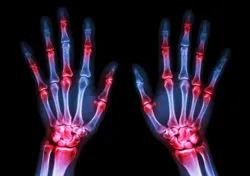

film x-ray both human's hands and arthritis at multiple joint (Gout,Rheumatoid)According to studies, the side effects of Uloric medication, used to treat gout, may include an increased risk of cardiac arrest or death.

Gout is a form of arthritis caused by a buildup of uric acid, which leads to redness, swelling, and severe joint pain. The medication Uloric works by reducing the amount of uric acid in the body, the acid associated with gout. While any medication will bring with it certain side effects, the side effects of Uloric medication may be more significant than a patient could reasonably expect.